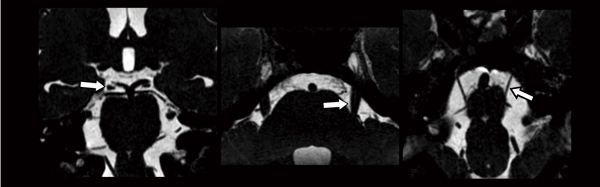

まず,3D-RSSGでは,高いSNRとT1コントラストを有効に利用するとともに,限定した領域をアキシャルで撮像し,動脈の強いin-flow効果を得ることで,解剖学的に細い神経と血管を良好に描出できる。図4aは,中脳レベルを動眼神経の走行と平行にリフォーマットした画像である。後大脳動脈(↑)がin-flow効果により高信号,中脳・動眼神経(←)が中等度信号,そして,脳脊髄液が低信号でそれぞれ描出されるため,神経と血管の関係を確認することができる。一方,T2系のコントラストを有する3D-BASG(図4b)も,詳細な構造を描出するのに有効なシーケンスである。3D-BASGは,脳脊髄液を高信号で描出でき,神経・血管系の構造を相対的に低信号として観察できる。そのため,流れのある脳脊髄液の信号変化を少なく撮像する工夫が必要となる。今回は,頭尾方向に流れている橋前槽の脳脊髄液をコロナルで撮像し(図5),必要に応じてリフォーマットする方法を紹介した。図6は,斜台とほぼ平行なコロナルで撮像した画像であり,流れによるアーチファクトがほとんどない。図の矢印は,動眼神経(左),三叉神経(中央),外転神経(右)を示し,周囲の血管との関係を明らかにするリフォーマット画像である。

図4 動眼神経と後大脳動脈の描出

図5 3D-BASGのCOR設定および素画像

図6 3D-BASGによる神経・血管の描出